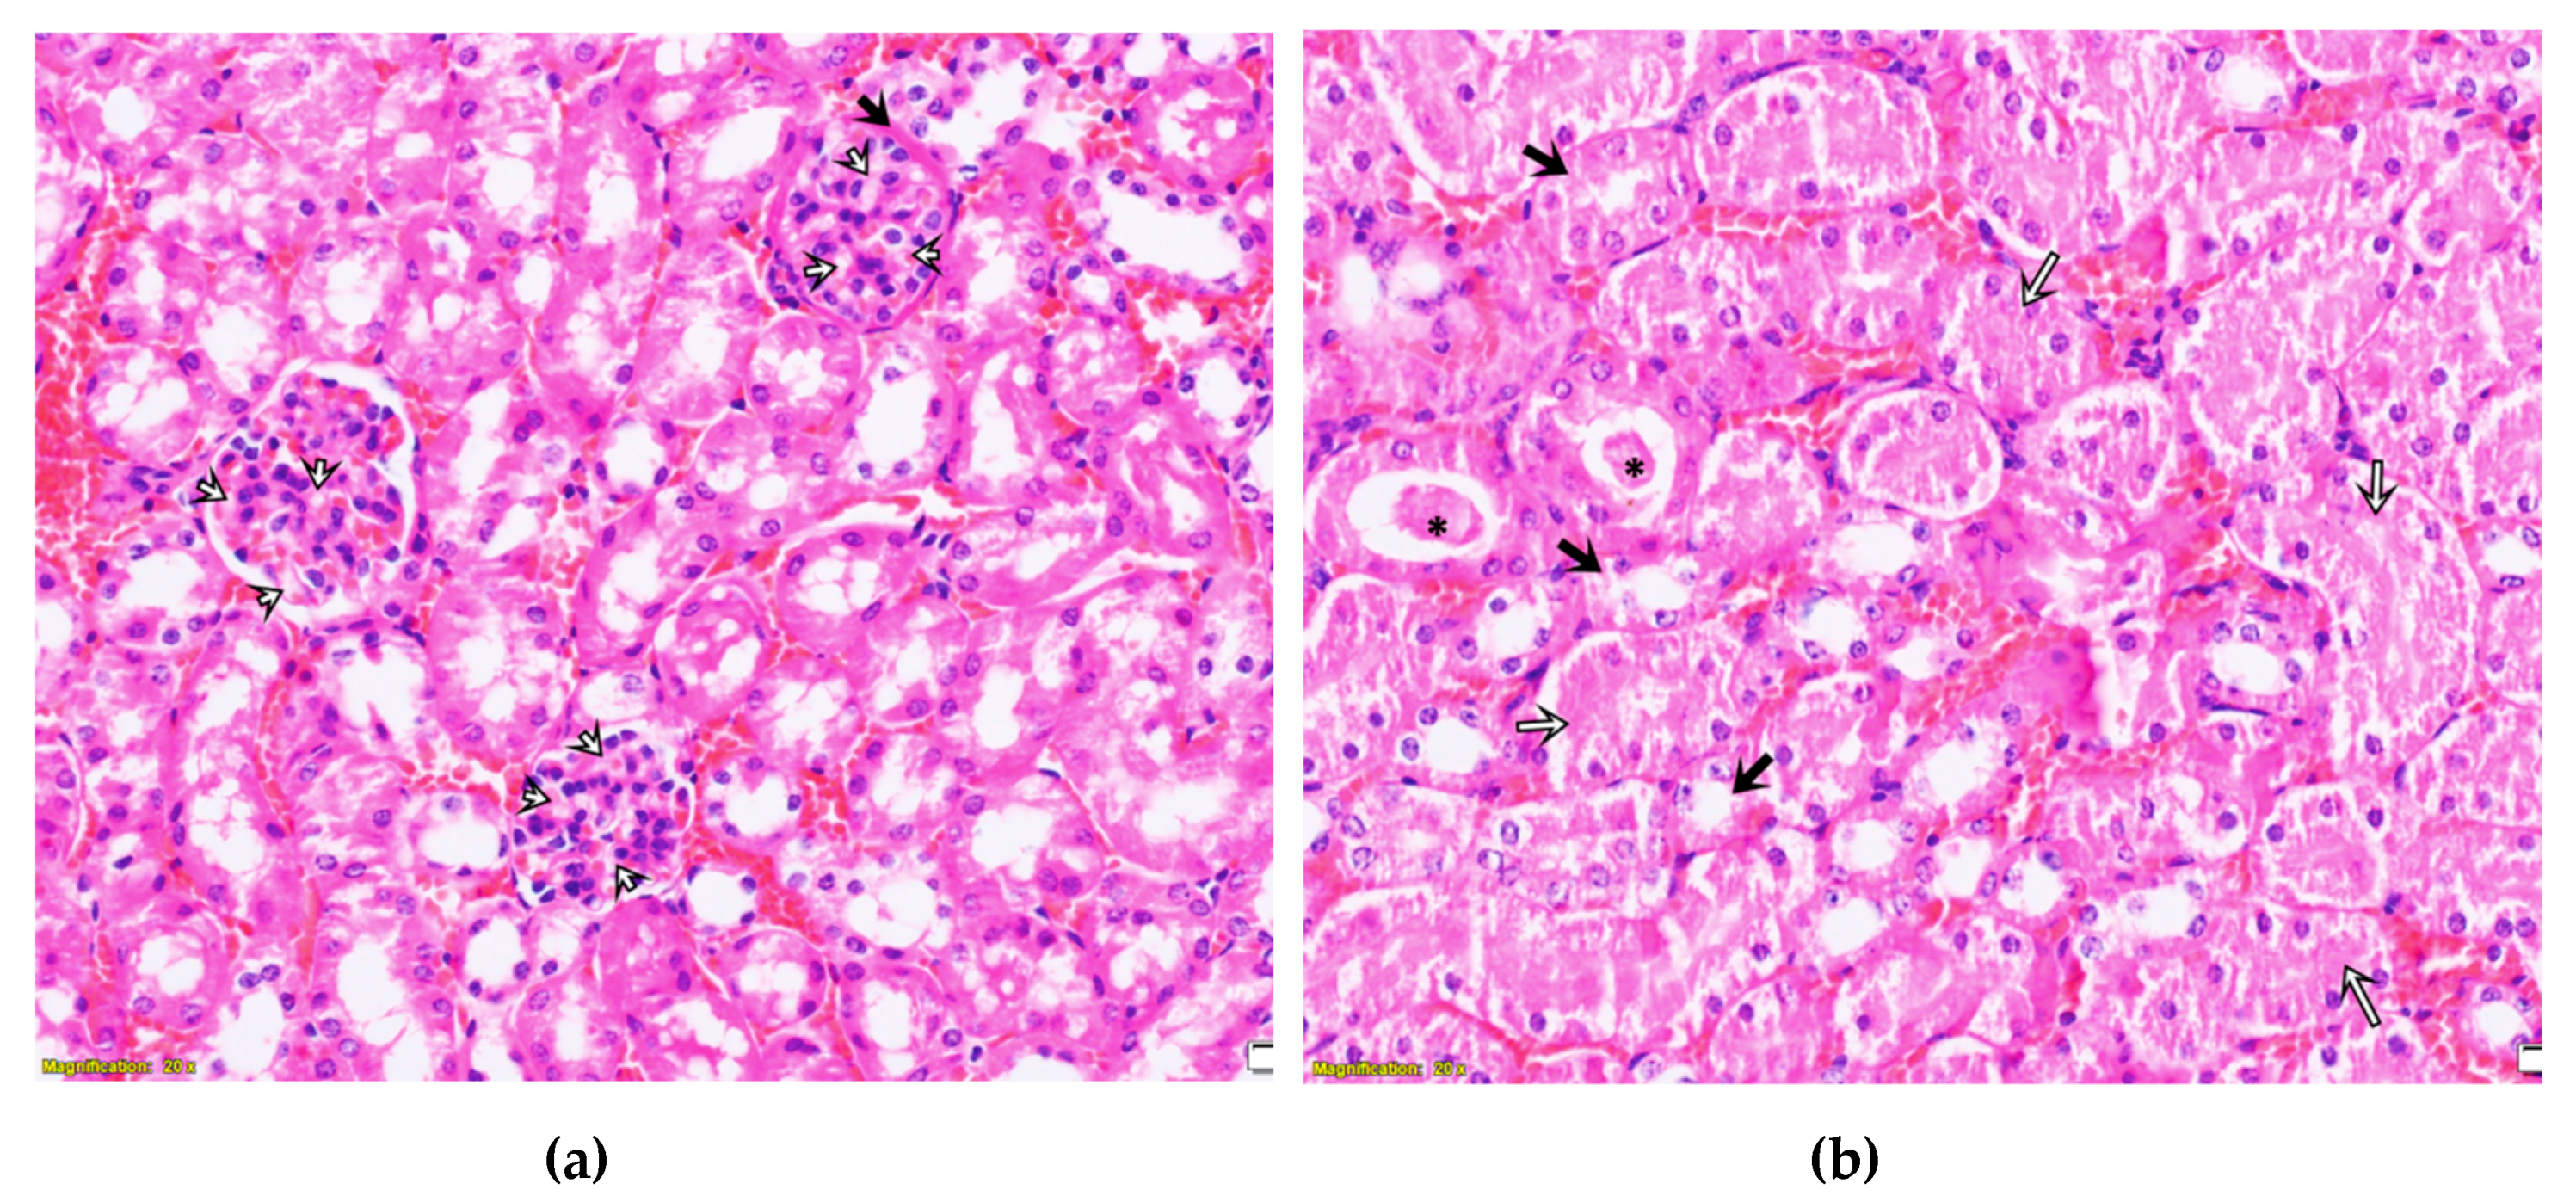

2.3. Purified LysM Lectin Impact to Kidney Morphology

3. Discussion

4.5.3. Histological Analysis of Kidney Samples